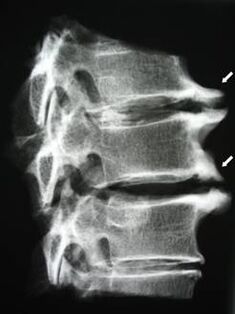

In the initial stage, osteochondrosis is detected using MRI.Later, the pathology can be diagnosed using radiography.A decrease in the distance between the vertebrae, pathological changes in the facet joints, and osteophytosis can be noticed on X-rays of the cervical spine.

| Cervical osteochondrosis | The appearance of pathological changes in one or more spinal movement segments.Impairment of spinal mobility, development of myofascial pain syndromes and pinching of spinal roots | Pain, paresthesia and motor disturbances in the neck region, spreading to the back of the head and upper limbs.Detection of characteristic changes in the spine on MRI and X-rays (osteophytes, reduced vertebral distance, signs of damage to intervertebral joints) |